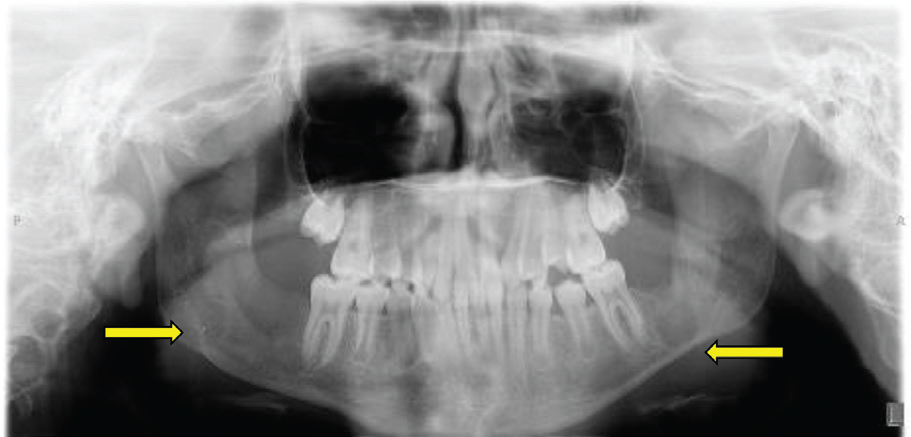

An 11-year-old female was referred by her dentist to our center’s oral maxillofacial surgeon to remove a jaw keratocyst, shown as a 2.5 × 2.5 cm radiolucent lesion of the right mandibular body (Figure 1: Dental Panorama X-ray). The patient was in sixth grade and enjoyed science and art.

Fig. 1. Panoramic dental radiograph showing multiple bilateral odontogenic keratocysts.

As part of the workup for the dental findings, she had a computed tomography (CT) of the head, which identified a calcified falx cerebri (Figure 2). A CT of the jaw (Figure 3) revealed multiple mini cysts and a large cyst in her lower jaw. Surgery removed a cyst from the right mandibular body and ramus associated with impacted tooth #31 pathology was consistent with an odontogenic keratocyst. After being seen by the surgeon, she was referred for genetic testing. Her past medical history was notable for a broken arm, benign hydrocephalus at around 8 months of age for which she had magnetic resonance imaging performed.